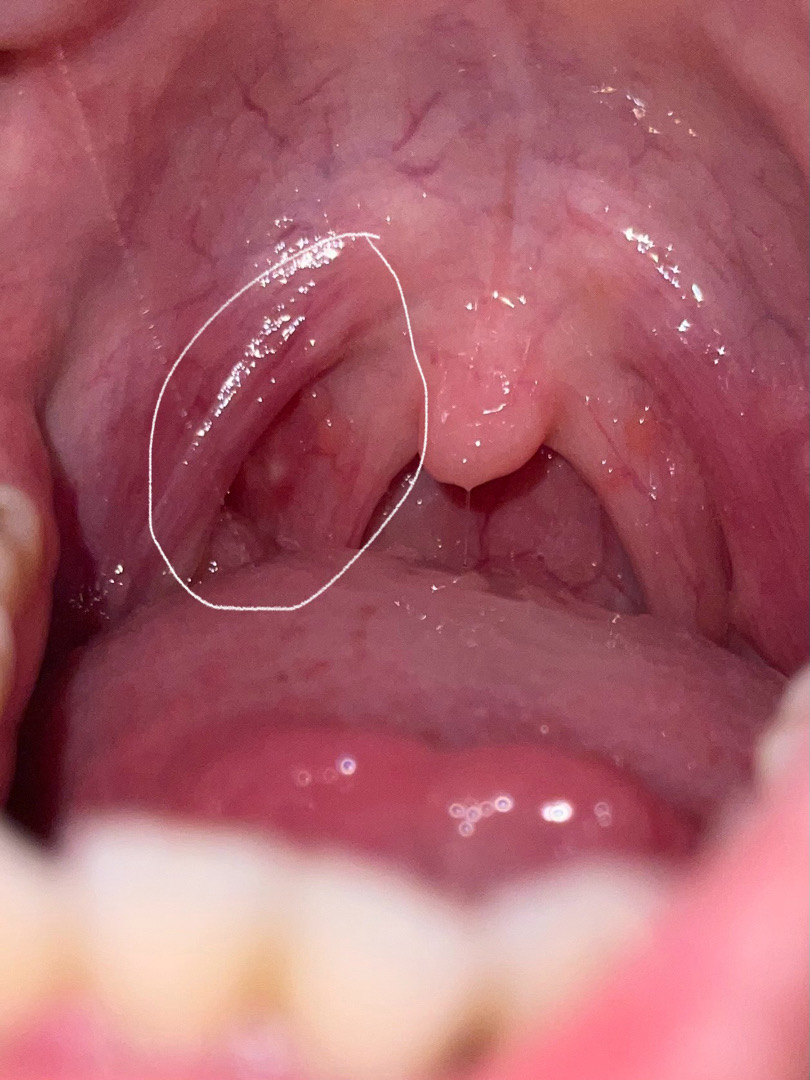

Dạ bác sĩ cho em.hỏi, con e lúc sơ sinh sau khi rụng rốn có bị ướt chồi rốn nhỏ. Bsi chỉ định bôi thuốc xanh, bôi gần 1 tháng thì khô ổn, gần đây 8 tháng e để ý lúc tắm xong hoặc bé giỡn bú no rốn có cục nhỏ ở giữa đỏ lên, để yên thì nhạt màu lại, rốn bé vẫn khô, vậy là có cần đi khám lại k ạ